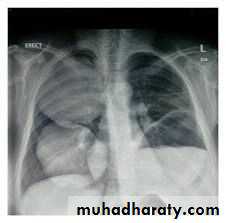

Pneumothorax

!! pneumothorax